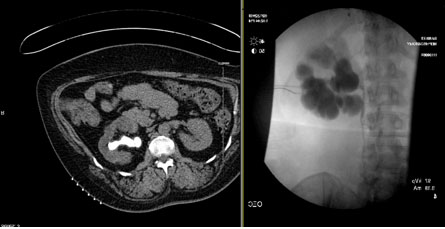

Clinical Image

Atypical acute obstruction of the urinary tract

Keywords: Acute kidney injury, Curvilinear reconstruction, Ureteral obstruction, Urinary catheter